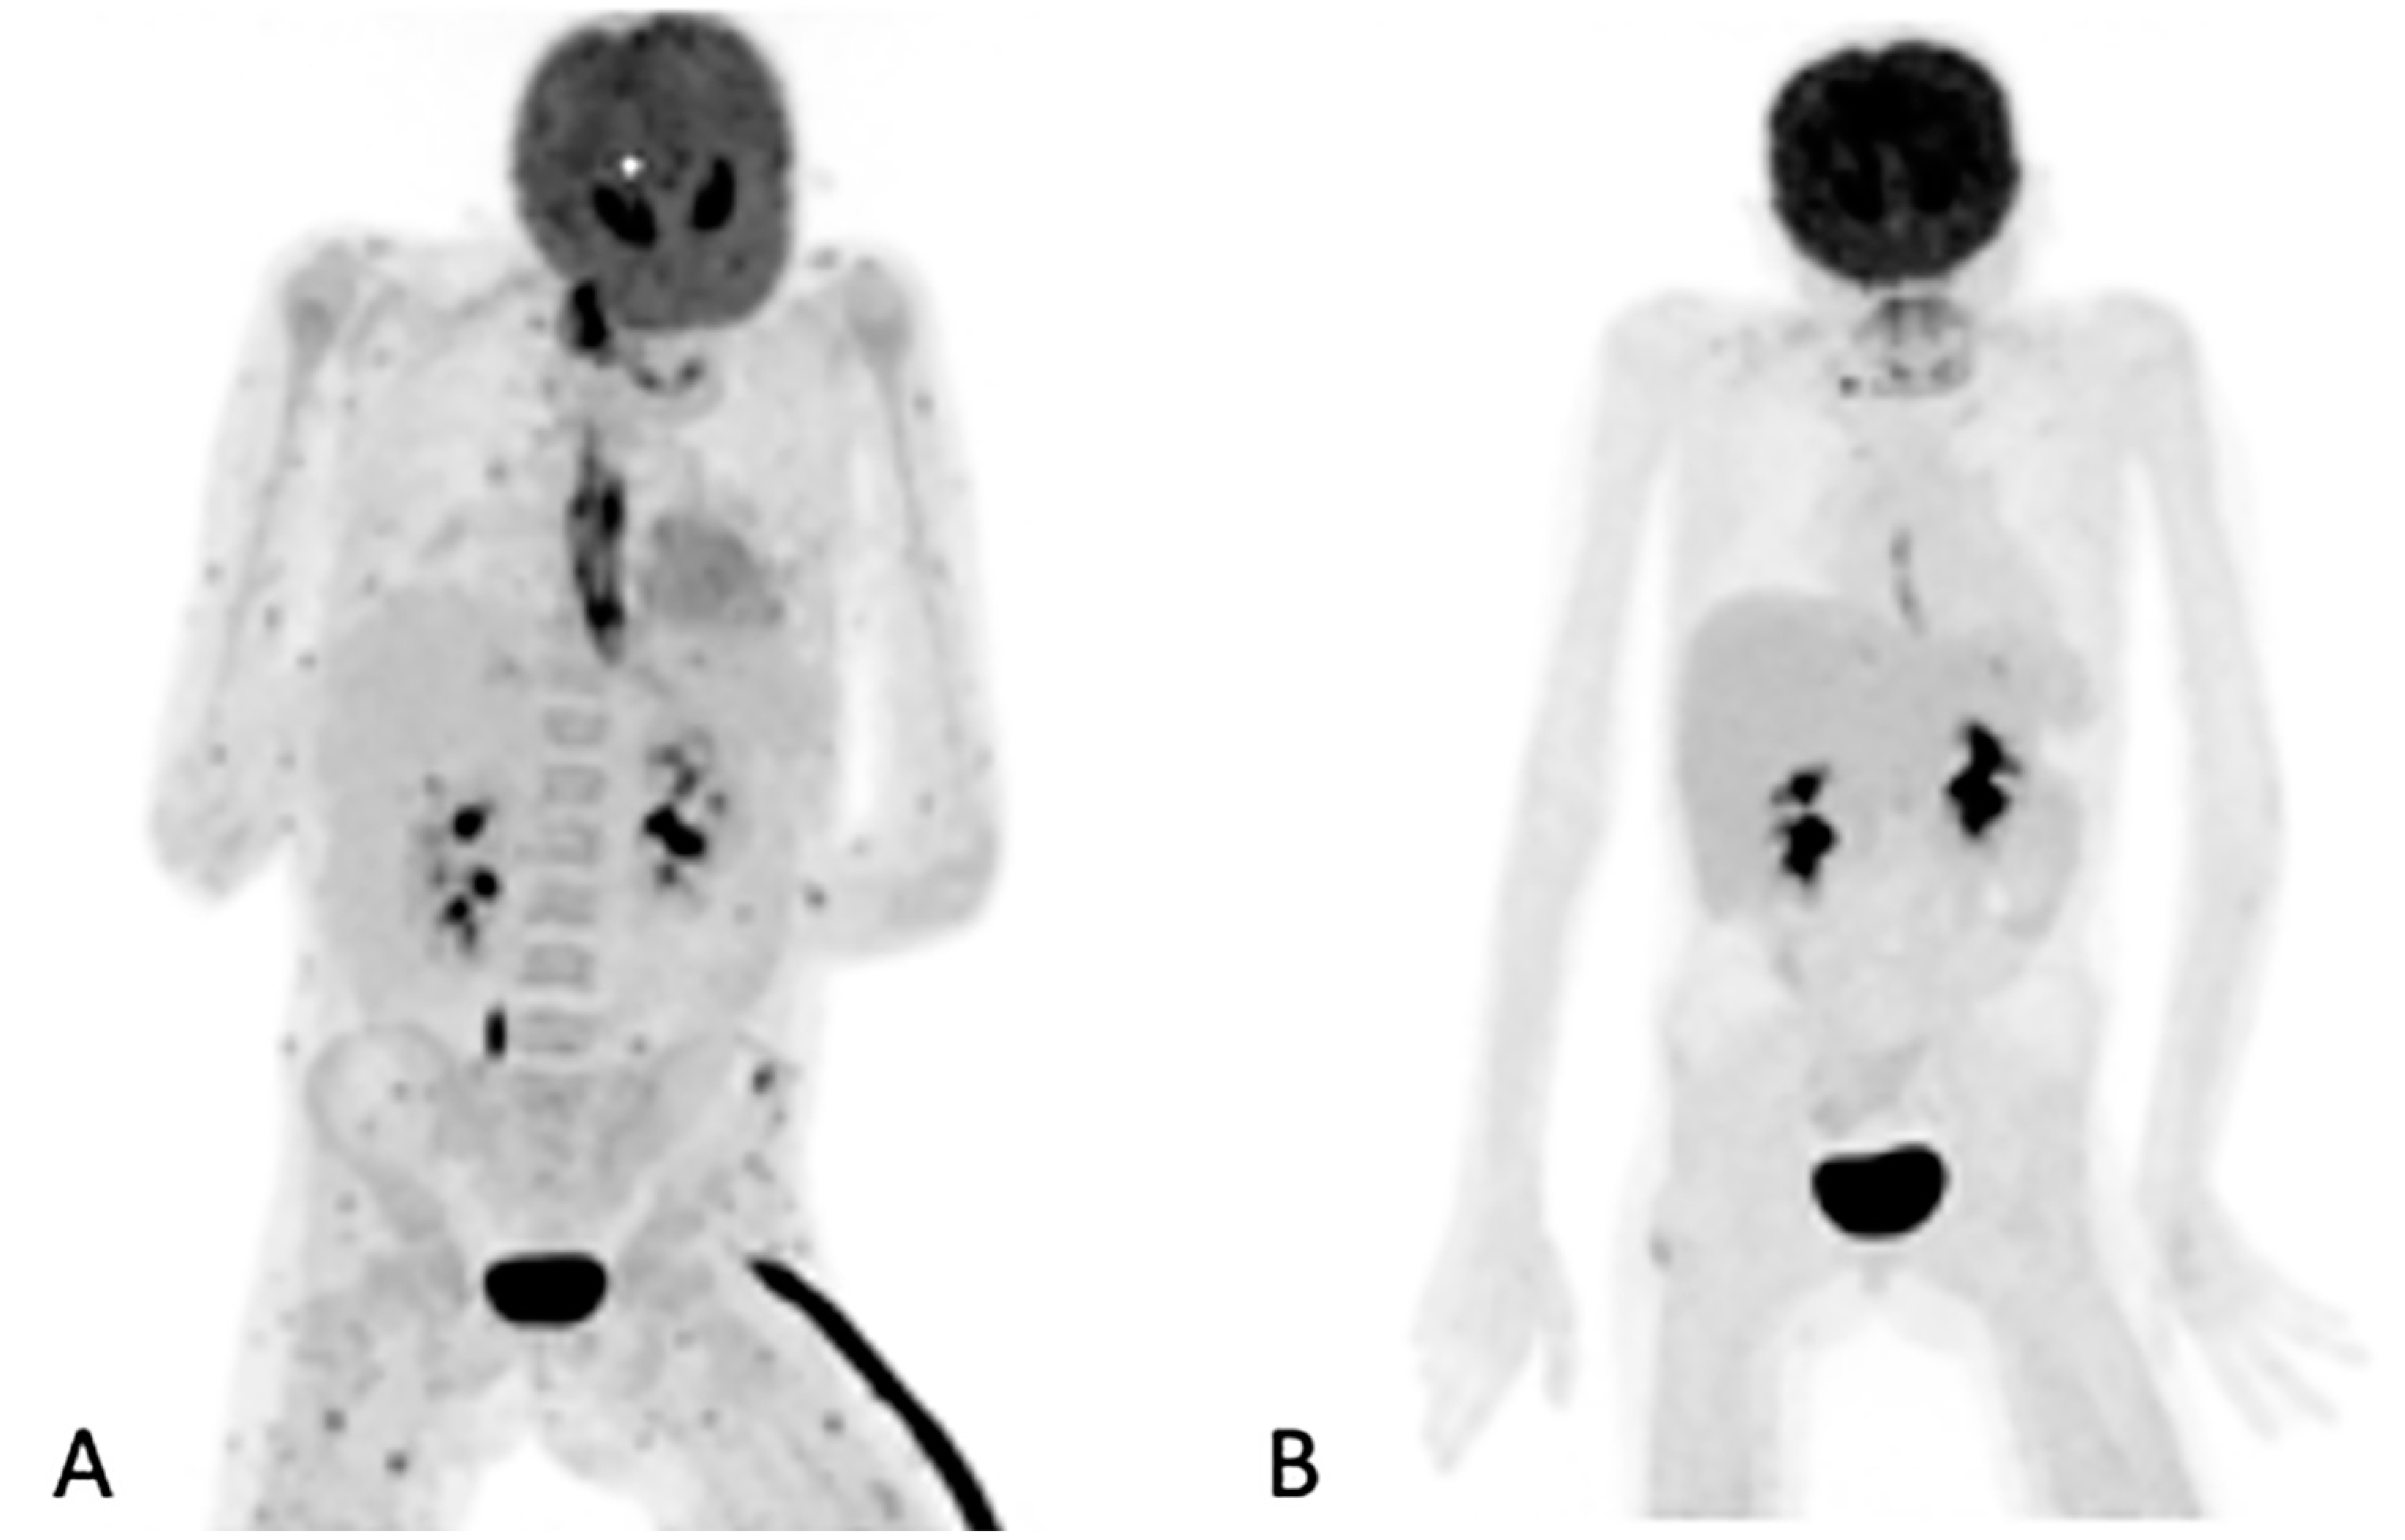

Of the 155 [18F]FDG PET/CT studies that were analyzed, 34 (22%) had no anatomy-based imaging (Table 3). Of the 34 [18F]FDG PET/CT studies that had no anatomy-based imaging, 28 (82.4%), were scans that were performed for the follow-up of IFI lesions that had been previously noted by previous imaging. The remaining four were two in patients being prepared for ASCT, and two in two patients for which [18F]FDG PET/CT had found metabolic activity in residual IFI lesions. Figure 2 shows a patient for which [18F]FDG PET/CT only was used to follow up because the IFI lesions could only be detected by the metabolic component of the study. Table 3 outlines the number of anatomy-based studies that were performed for each [18F]FDG PET/CT scan studied and the concordance between the [18F]FDG PET/CT and anatomy-based study at the site of the study.

Figure 2.

Maximum intensity projection (MIP) of [18F]FDG images of a 10-year-old girl on chemotherapy for acute lymphocytic leukemia. She had a persistent fever unresponsive to antibiotics. HR CT not shown (was unremarkable). The initial study (A) revealed widespread, multiple, small, metabolically active foci in the muscles and esophagitis, which were later found to be due to Candida dubliniesis upon biopsy. The lesions were not detected by the corresponding CT of the [18F]FDG PET/CT study. A follow-up [18F]FDGPET/CT study (B) after 6 weeks of antifungal treatment showed a very good metabolic response, with a single residual focus in the right gluteus and the resolution of the esophagitis. No anatomy-based study was performed together with the follow-up [18F]FDG PET/CT study (B).